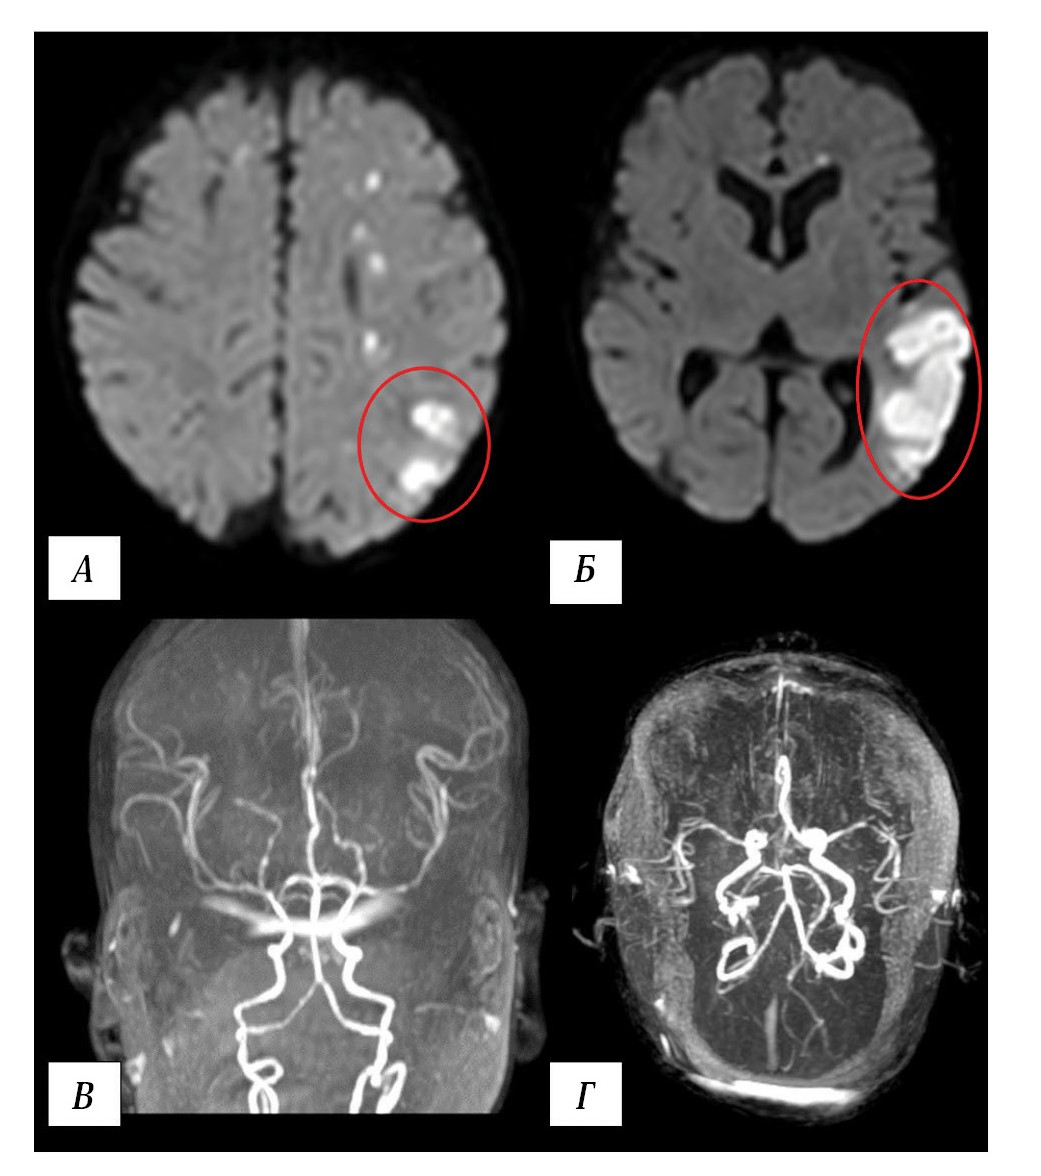

On day 2 postoperatively, focal motor epileptic seizures developed, manifesting as clonic jerking of the upper extremities (D < S), which were managed with midazolam infusion at 0.2 mg/kg/h and intravenous levetiracetam at 25 mg/kg/day. Emergency MRI revealed a watershed infarction zone in the left cerebral hemisphere (Fig. 8).

Fig. 8. Results of patient V. MRI on day 2 postoperatively.

A, B — brain MRI. Right DWI, axial plane. Watershed infarction zone in the left cerebral hemisphere (red ovals), multiple small ischemic foci. C, D — MR angiography, 3D reconstruction. Intracranial arterial blood flow remains intact.